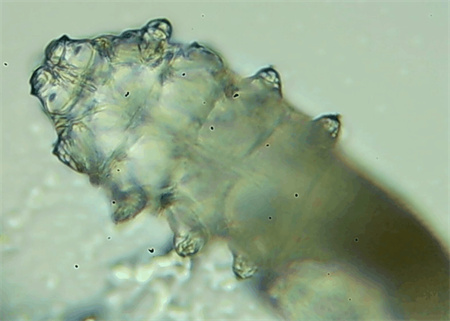

這種螨蟲叫做蠕形螨,他們通常呈乳白色、半透明的細(xì)長狀,擁有四對腳。它們跟被子上的塵螨可不是同一種。

這些蠕形螨主要寄生在面部、頭皮、眼睛的睫毛毛囊、睫毛皮脂腺,以及瞼板腺里,以睫毛囊上皮細(xì)胞、腺體內(nèi)脂質(zhì)為食物。因此,即使經(jīng)常換洗床單、衣物,也可能會(huì)有蠕形螨。